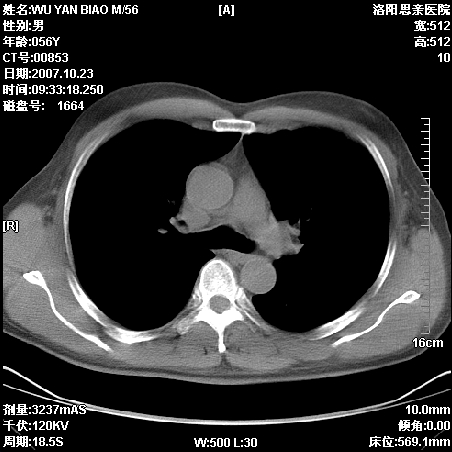

标题: CT10160:M56Y,体检发现,病人无不适,病人随访中 [打印本页]

标题: CT10160:M56Y,体检发现,病人无不适,病人随访中

后上纵隔占位,与肺交界清,宽基底附着脊柱,密度均匀,局部骨质无明确改变.

考虑;神经源性肿瘤,---起源交感n链?,不除外肠源性囊肿.

1、病灶在后纵隔脊柱旁沟内,此处是神经原性肿瘤的好发部位

2、病灶边缘光滑整齐,更说明病灶来于纵隔,由于有胸膜的包裹所以才导致这么光滑的边缘

3、病灶内的密度均匀